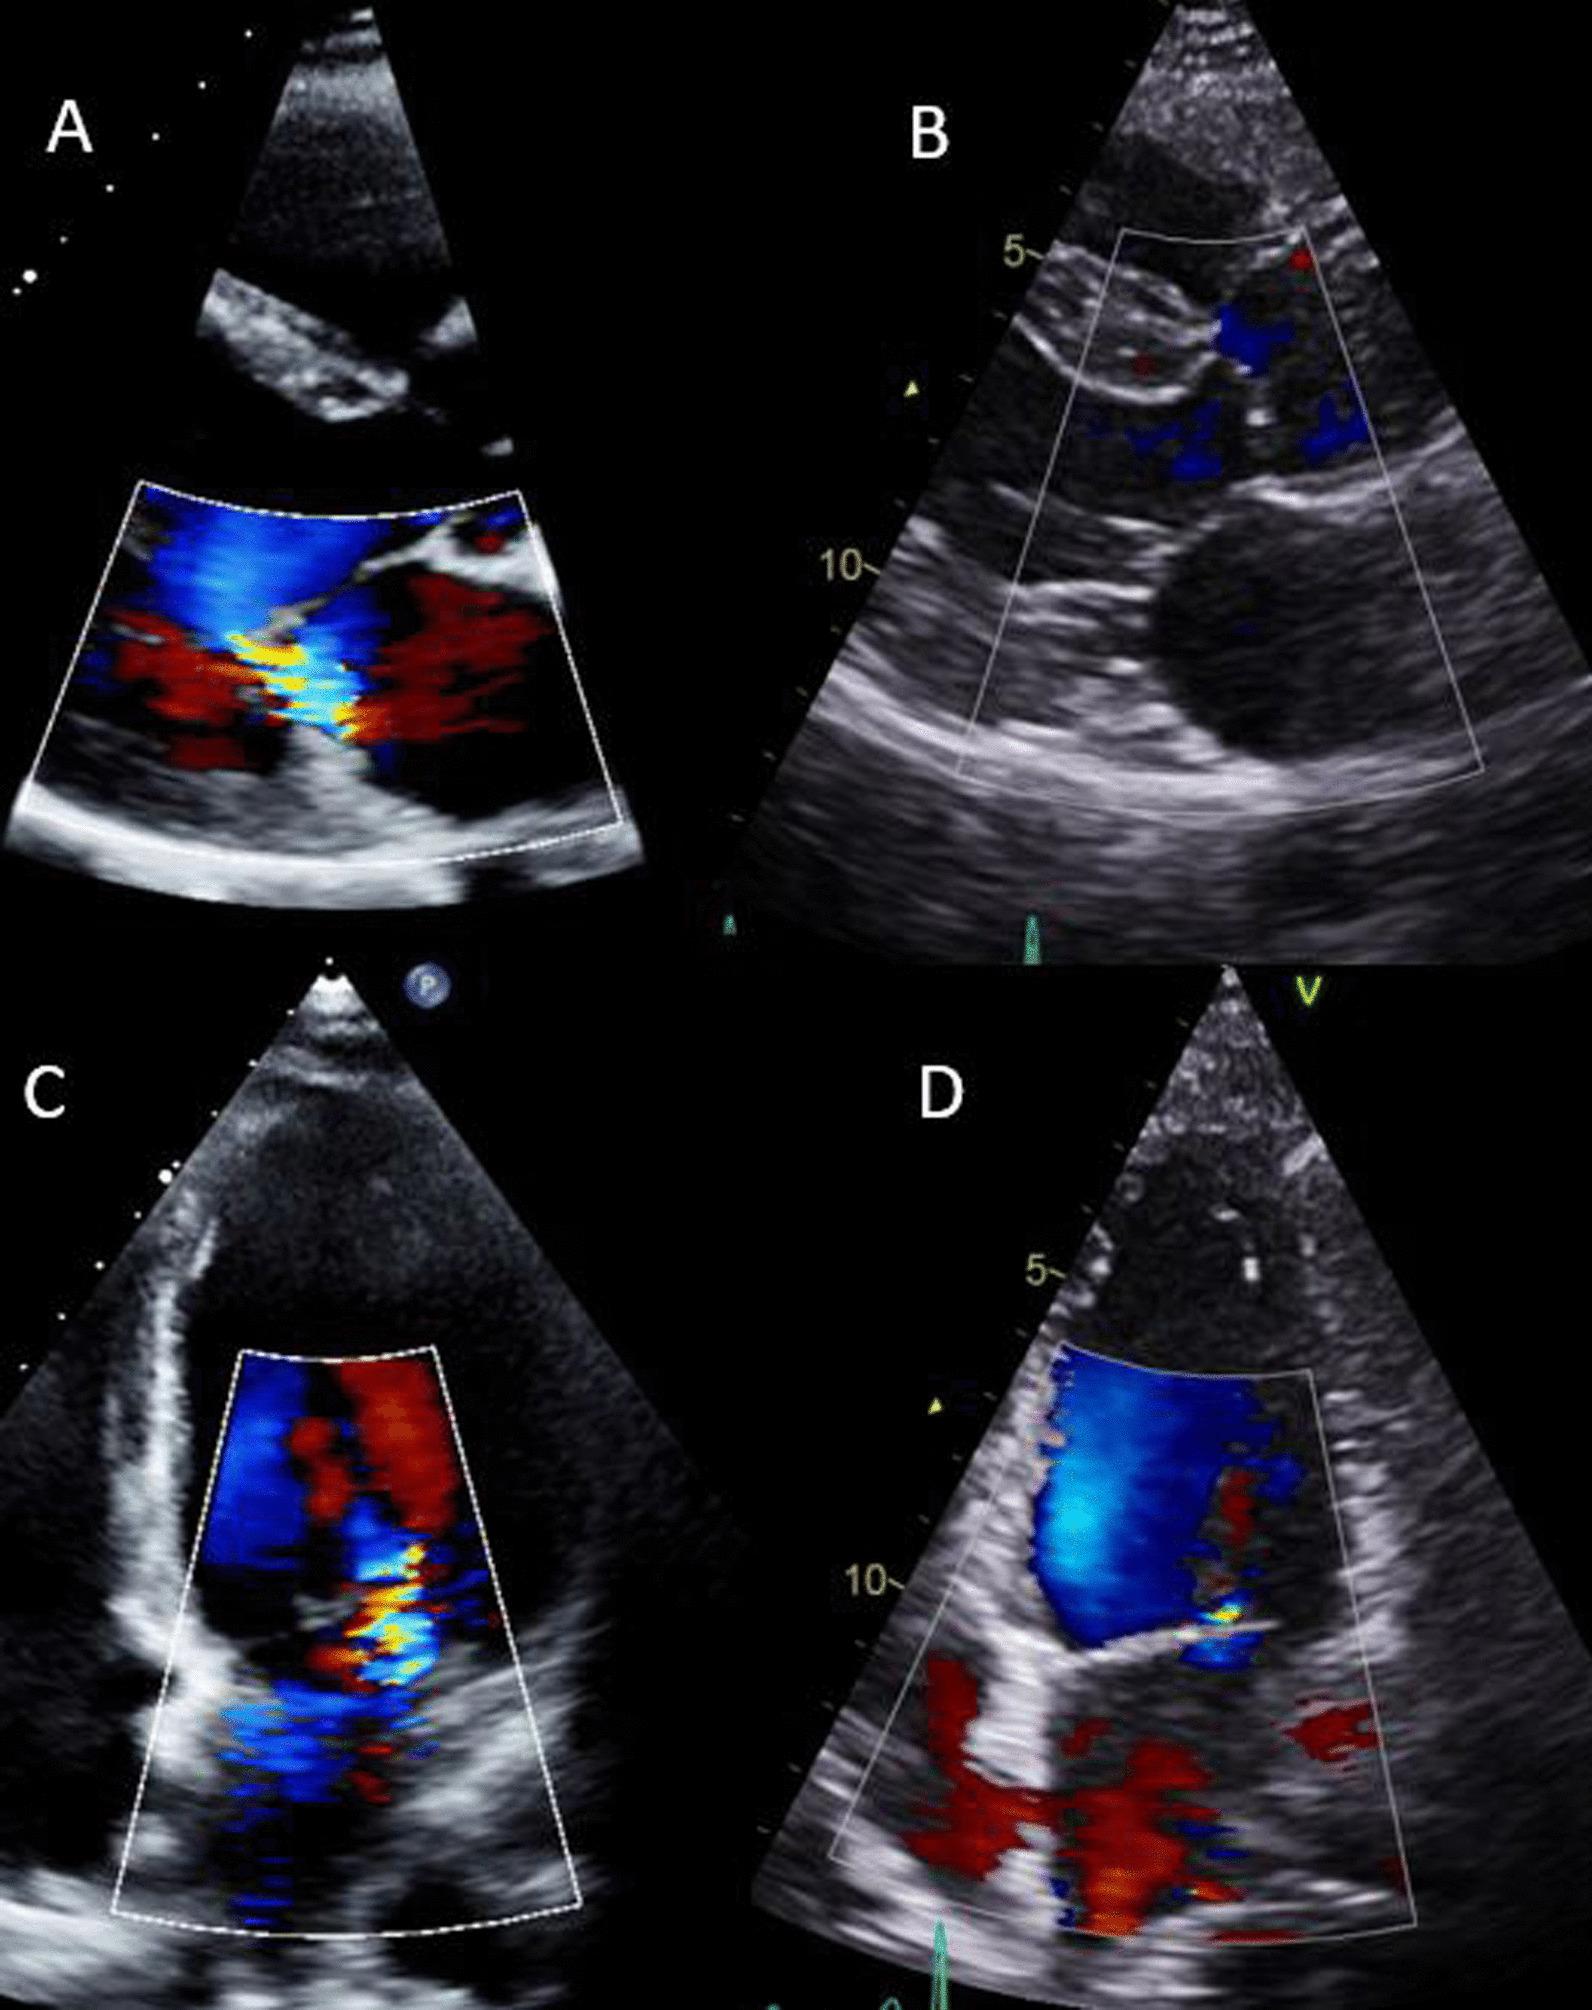

Pregnancy is a dynamic process associated with profound hormonally mediated haemodynamic changes which result in structural and functional adaptations in the cardiovascular system. An understanding of the myocardial adaptations is important for echocardiographers and clinicians undertaking or interpreting echocardiograms on pregnant and post-partum women. This guideline, on behalf of the British Society of Echocardiography and United Kingdom Maternal Cardiology Society, reviews the expected echocardiographic findings in normal pregnancy and in different cardiac disease states, as well as echocardiographic signs of decompensation. It aims to lay out a structure for echocardiographic scanning and surveillance during and after pregnancy as well as suggesting practical advice on scanning pregnant women.

妊娠是一个动态过程,与激素介导的显著血流动力学变化相关,这些变化导致心血管系统的结构和功能适应。了解心肌适应情况对于为孕妇和产后妇女进行超声心动图检查或解读超声心动图的超声心动图医生和临床医生来说很重要。本指南代表英国超声心动图学会和英国母胎心脏病学会,回顾了正常妊娠和不同心脏疾病状态下预期的超声心动图表现,以及失代偿的超声心动图征象。其目的是为妊娠期间及产后的超声心动图扫描和监测制定一个框架,并就扫描孕妇提供实用建议。